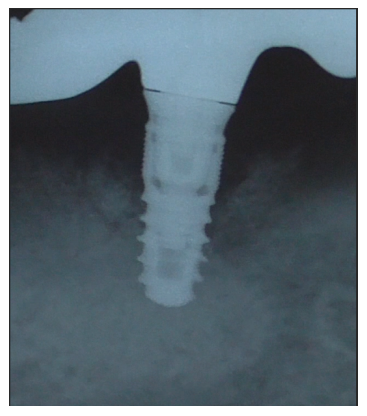

Radiographically, we can observe an increase in bone level around the implant (Figure 46).

Figure 46

Furthermore, a probing around the implant is performed, showing a reduction in pocket depth and bleeding (Figures 47,48).

Figure 47

Figure 48

In our case report, a regenerative/reconsructive surgical procedure was chosen with the goal of not only conditioning and decontaminating the implant surface but also resolve the osseous defect [16]. In accordance with the literature, a flap was raised to access the defect and perform debridement [22]. Decontamination of implant threads was performed using an ultrasonic instrument to eliminate biofilm adhering to surfaces and reduce bacterial colonization [23]. To enhance site debridement and minimize colonization by pathogenic microbial agents, the ES004E insert patented by Dr. Tarquini for Esacrom was chosen. Thanks to its shape, a strong cavitation effect is achieved, improving site disinfection. The goal of peri-implantitis therapy is to control the bacterial infection causing tissue destruction [18]. For this reason, additional disinfection procedures were performed. In accordance with the literature, 24% EDTA was chosen as an adjunct to mechanical biofilm decontamination [24]. Given the importance of maintaining a pH ≥ 3 to prevent morphological changes and corrosion of the implant surface that can hinder re-osseointegration, the exposure duration to this chemical agent was one minute [25]. To further reduce microbial load, ambramicin powder was also used. Clinical studies have indeed demonstrated the effectiveness of tetracyclines as adjuncts in regenerative surgery procedures [26]. Autologous bone, harvested from an adjacent area to the implant site, allogenic bone, hyaluronic acid, and polynucleotides were used as bone fillers [16]. Before proceeding with osseous defect filling, fibrin sponges were placed at the site’s bottom, allowing radiographic assessment of effective bone regeneration, leveraging the radiotransparency of this material. Results in the 6-month post-operative follow-up showed the absence of clinical signs of inflammation (bleeding and suppuration) detectable through objective examination and use of a periodontal probe. Radiographically, significant bone remineralization around the implant was visible clinically. Results at 1-year post-operative follow-up showed a clinically significant reduction in probing depth with an absence of bleeding. Additionally, radiographically, there is a clinically significant increase in bone around the implant threads.